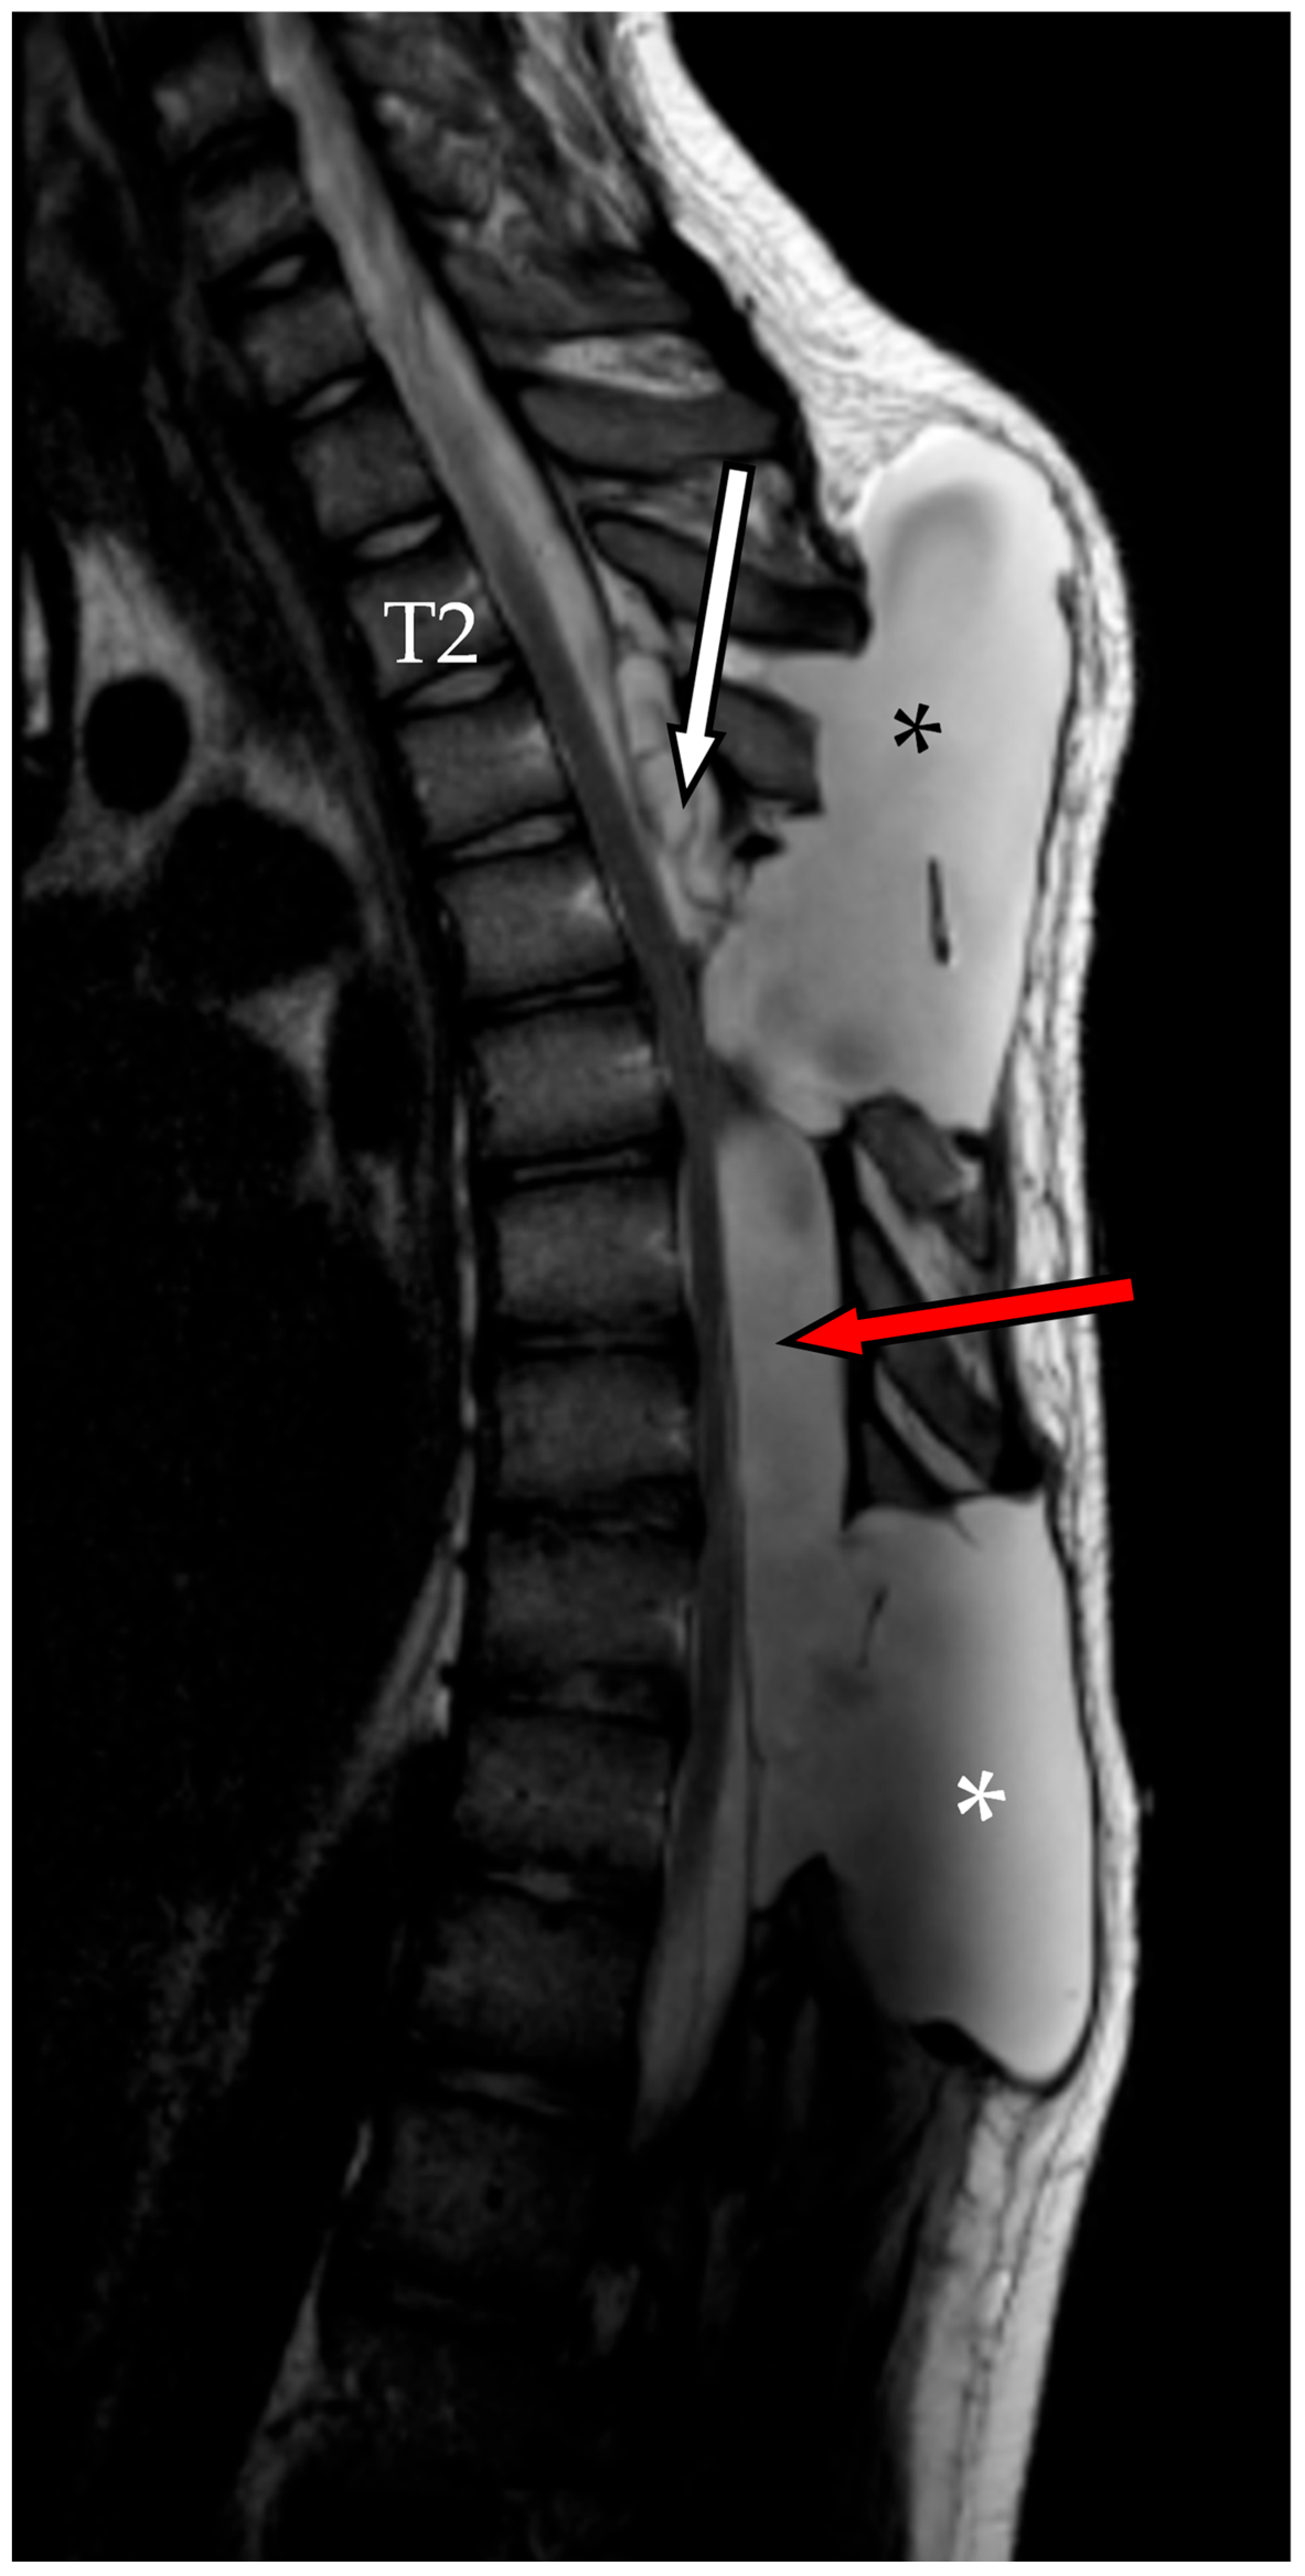

2.3. Second Admission

2.4. Second Follow-Up